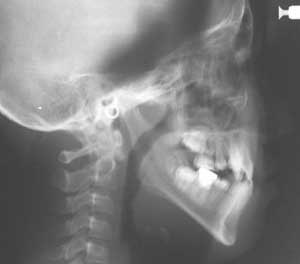

頭部X線規格写真(セファログラム)

X線の光源と被写体(人物)およびフィルム面までの距離が一定の条件の下に規格されており、同じ条件で客観的に本人と正常者との比較あるいは本人の経時的変化 (成長変化や治療による位置の変化)を比較することができます。